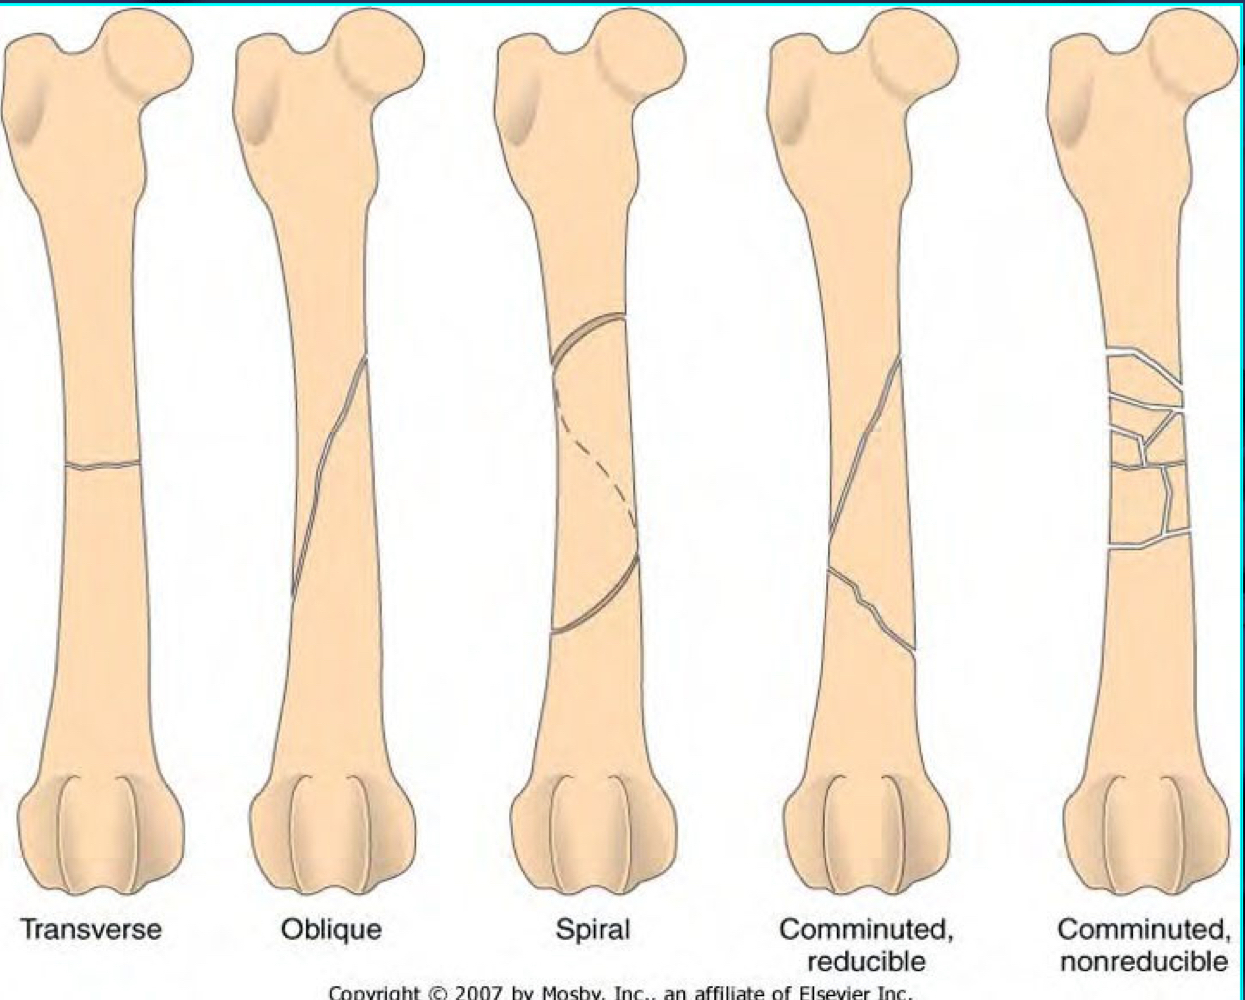

What are transverse, oblique, and spiral fractures?

TRANSVERSE = angle of the fracture line is perpendicular to the long axis of the bone

OBLIQUE = angle of the fracture line is on a diagonal to the long axis to the bone

SPIRAL = fracture line curves around the bone

What is the difference between reducible and irreducible fractures?

REDUCIBLE - able to be put back into alignment, usually more simple and low energy

IRREDUCIBLE - can’t use pins and plates to correct small splintering of bones, cannot be put back into alignment (jigsaw puzzle)